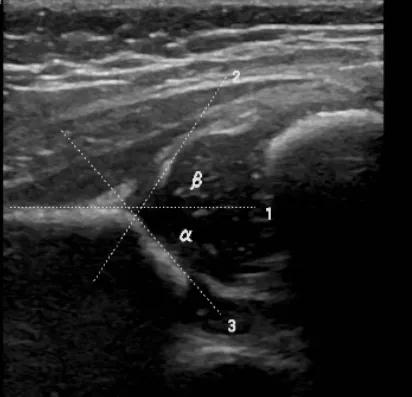

mr 45°; 5.髋关节脱位α 45°,β无法测量,mr无法测量.